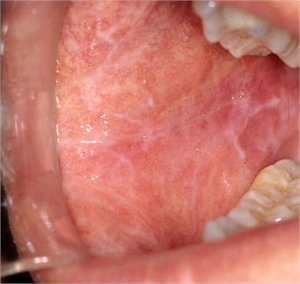

Wickham's striae is associated with lichen planus irrespective of ethnicity, race and gender. In the oral cavity, Wickham's striae can be seen in the inner linings of the cheek (buccal mucosa), gingiva, lips and tongue. Investigative procedures like dermatoscopy or application of certain oils and stains can help in identification of Wickham's striae. In lichen planus, Wickham's striae are seen on the purplish papules seen in the oral cavity.

It is still unclear at what stage of the development of lichen planus do Wickham's striae form. In his description of the papules of lichen planus, Wickham stated that the affected surface can be divided into two parts. One is a reddish component and the other is a grayish component. The reddish areas lie underneath, over which the grayish layer appears. It is from the grayish area where the lace-like lines originate. The extent of these striae vary in each case. In some cases it is restricted to the papule whereas in some more extensive cases, the whitish lines are present at the length of the buccal mucosa.

The direction of the striae is not fixed either and has been most often described as tree-like configuration. Till date, researchers have established six patterns in which Wickham's striae may present itself. These are circular, reticular (branched), radial linear, globular, perpendicular and veil-like. The presence of Wickham's striae is usually bilateral. This means that it is more often present on both sides of the mouth.